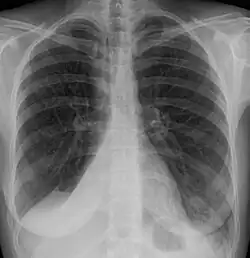

Atelectasis of a person's right lung | |

Atelectasis is the partial collapse or closure of a lung resulting in reduced or absence in gas exchange. It is usually unilateral, affecting part or all of one lung.[2] It is a condition where the alveoli are deflated down to little or no volume, as distinct from pulmonary consolidation, in which they are filled with liquid. It is often referred to informally as a collapsed lung, although more accurately it usually involves only a partial collapse, and that ambiguous term is also informally used for a fully collapsed lung caused by a pneumothorax.[1]

Clinically significant atelectasis is generally visible on chest X-ray; findings can include lung opacification and/or loss of lung volume. Post-surgical atelectasis will be bibasal in pattern. Chest CT or bronchoscopy may be necessary if the cause of atelectasis is not clinically apparent. Direct signs of atelectasis include displacement of interlobar fissures and mobile structures within the thorax, overinflation of the unaffected ipsilateral lobe or contralateral lung, and opacification of the collapsed lobe. In addition to clinically significant findings on chest X-rays, patients may present with indirect signs and symptoms such as elevation of the diaphragm, shifting of the trachea, heart and mediastinum; displacement of the hilus and shifting granulomas.[13]